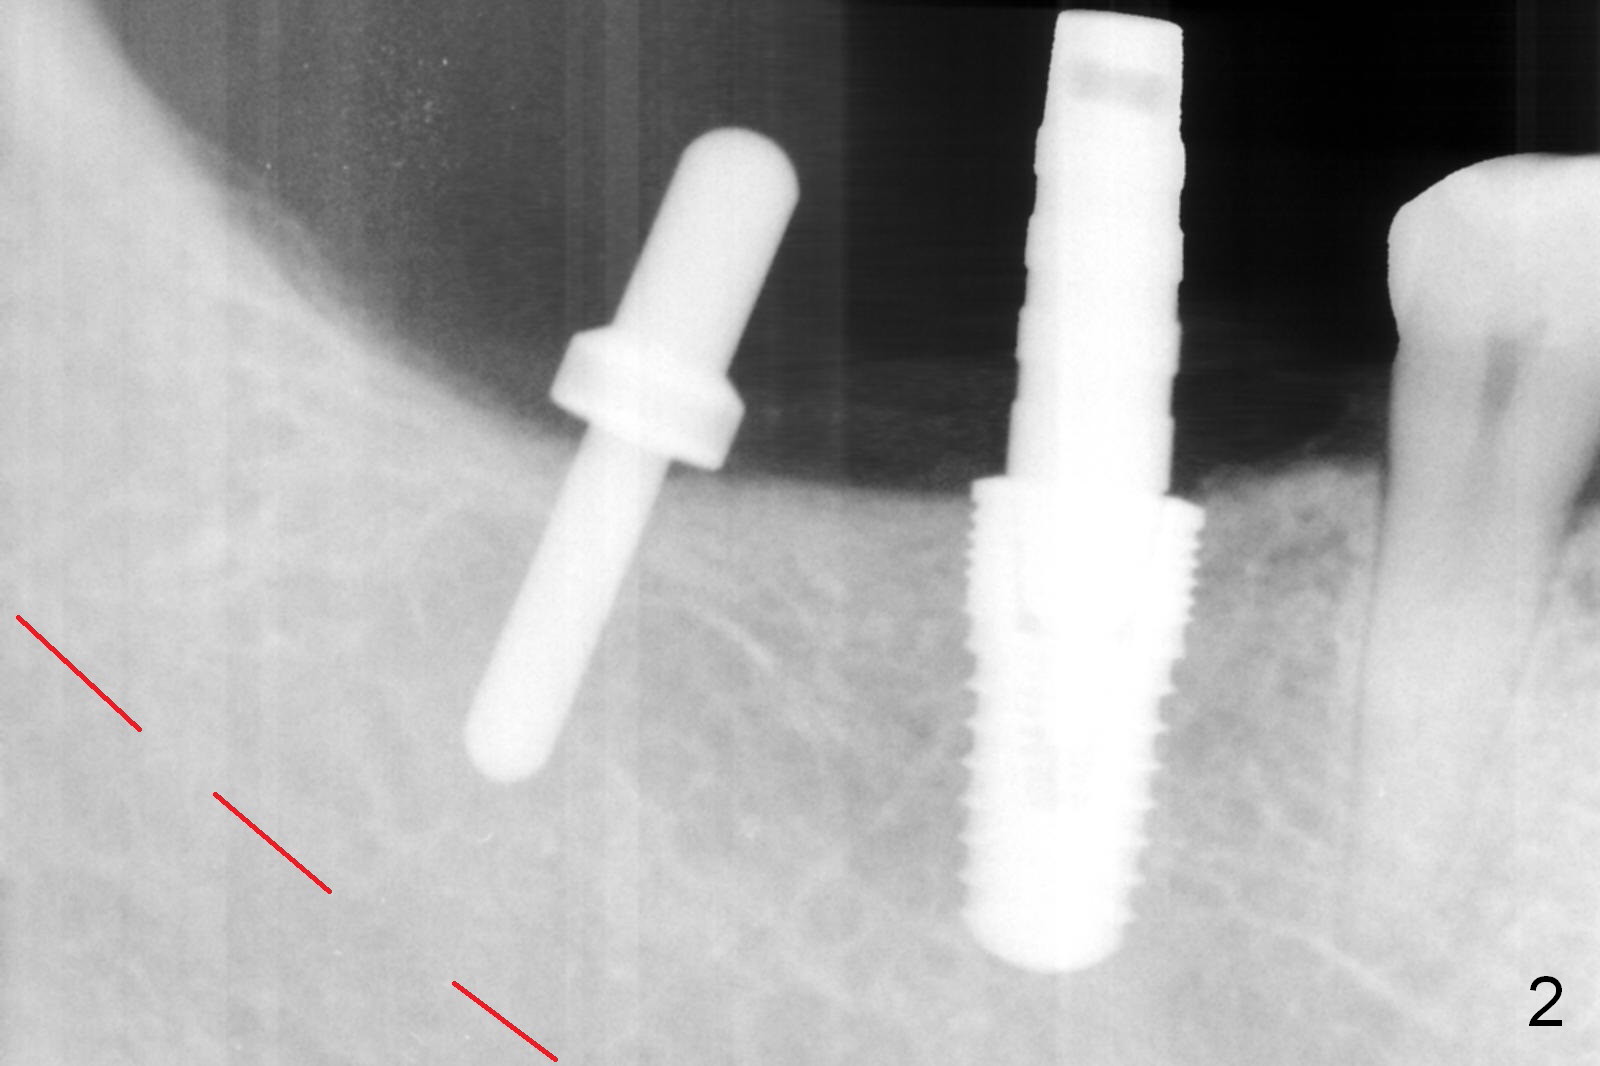

After vacation, the nervous patient returns for #30, 31 implant placement. After infiltration anesthesia, initial osteotomy goes on smoothly at the depth of 10 and 8 mm, respectively (Fig.1). Depth gauge post 5x10 mm drilling shows that the distal osteotomy at #30 is 14 mm in spite of depth control (using drill stopper). Damage the Inferior Alveolar Canal or Mental Loop? Since hemorrhage is moderate, a 5x10 mm submerged implant is placed without discomfort from the patient (Fig.2); when the osteotomy at #31 is being enlarged with 2/2.7 mm pilot drill at 8 mm, the patient experiences severe pain without any obvious reason. The infiltration anesthesia is increased with Articaine and Marcaine. The depth of the osteotomy reduces at 6 mm. The osteotomy and 5.9x6 mm implant placement is done in a slow and gentle manner (Fig.3,4). The bone density mesioapical to the implant at #30 is low (Fig.3 dot line, Fig.5 (CBCT, ≤50 units) *)). This may account for apparent increase in the osteotomy at #30. The soft bone gives in to the depth gauge!